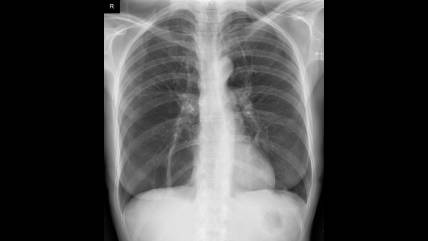

If these proteins are weak or defective, it can lead to a higher risk of chronic obstructive pulmonary disease (COPD) and start to show emphysema symptoms that make it hard to push air out of the lungs. It can also result in chronic bronchitis.

Due to your parents' defective genes, you have a low level of AAT protein in your blood. Instead of flowing into your bloodstream, the protein can build up in your liver, causing liver disease. Lung illness is caused by a lack of AAT protein in your system. You may also have a slight chance of acquiring lung and liver diseases, especially if you smoke.